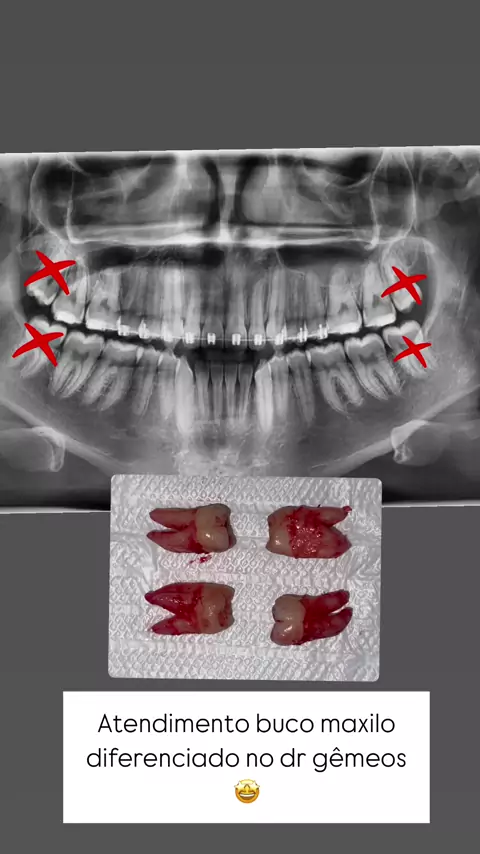

Já sofreu com seu siso? Em apenas 45 minutos conseguimos remover os 4! Tem medo ou já teve trauma com siso? Manda uma mensagem ou marca a gente aqui! Vamos tirar suas dúvidas